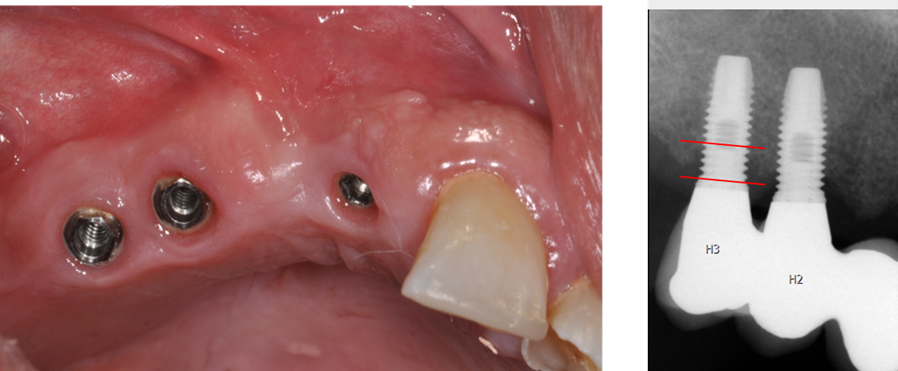

Att behandla tandlöshet med dentala implantat och återskapa förmåga att tugga, tala och ett vackert leende är en etablerad behandlingsmetod vilken har ett gott stöd i vetenskapen [1-3]. Årligen behandlas ca 40 000 patienter med dentala implantat inom det statliga tandvårdsstödet i Sverige (Försäkringskassan och TLV). Trots de goda vetenskapliga resultaten, förekommer såväl biologiska som tekniska komplikationer, vilket kan innebära stora, negativa konsekvenser för patienterna.

En stor mängd publicerade vetenskapliga studier visar att behandlingar med dentala implantat har hög lyckandefrekvens [4-7]. Studier visar även att behandlingarna kan medföra såväl biologiska [8, 9] som tekniska komplikationer [10-12], vilket kan innebära stora, negativa konsekvenser för patienterna. Behov av ytterligare kunskap finns för att vidare kunna förbättra behandlingarna och förhindra uppkomsten av komplikationer.

• Förbättrad spårbarhet enligt EU 2017/745 om medicintekniska produkter

• Ökad patientsäkerhet